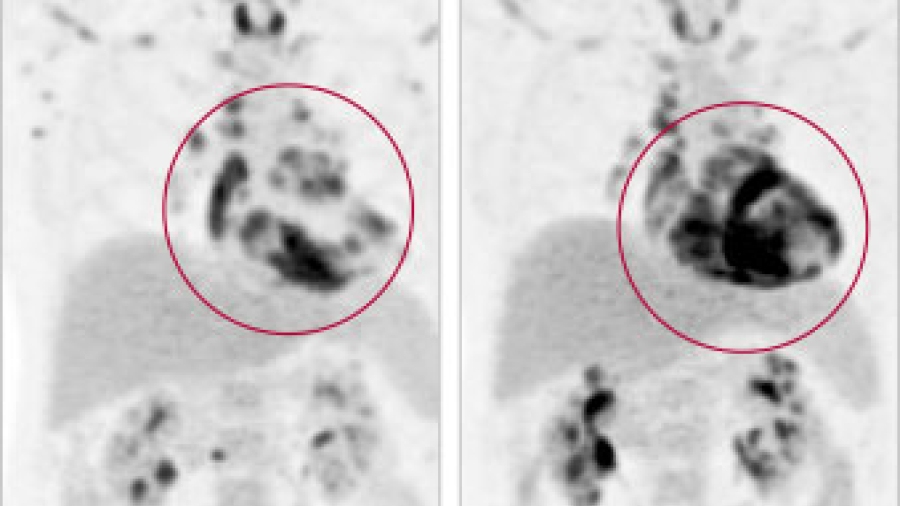

MRI

February 17, 2015

Completing the Cardiac Imaging Fleet with MRI